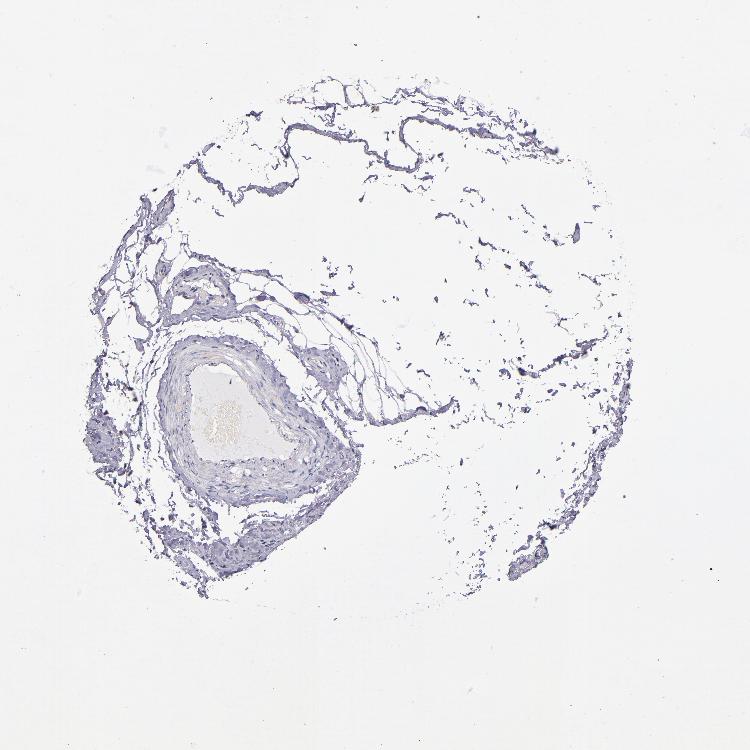

SOFT TISSUE 2 - Antibody stainingi

Antibody staining in the annotated cell types in the current human tissue is reported as not detected, low, medium, or high, based on conventional immunohistochemistry profiling in selected tissues. This score is based on the combination of the staining intensity and fraction of stained cells.

Each image is clickable and will lead to virtual microscopy that enables deeper exploration of all samples and also displays staining intensity scores, fraction scores and subcellular localization as well as patient and tissue information for each sample.

Antibody HPA001619Antibody HPA002078

Fibroblasts Not detectedMedium

Peripheral nerve Not detectedMedium